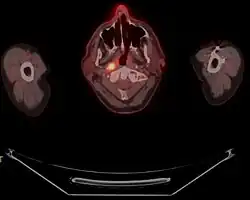

-

Stage T1 nasopharyngeal cancer -

Stage T2 nasopharyngeal cancer -

Stage T3 nasopharyngeal cancer -

Stage T4 nasopharyngeal cancer